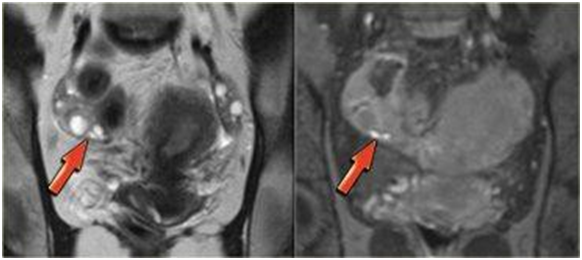

Hình 2. Nang lạc nội mạc buồng trứng (P)

Hình 3. Coronal T2W và T1FS: các nốt lạc nội mạc ở bề mặt buồng trứng (P)